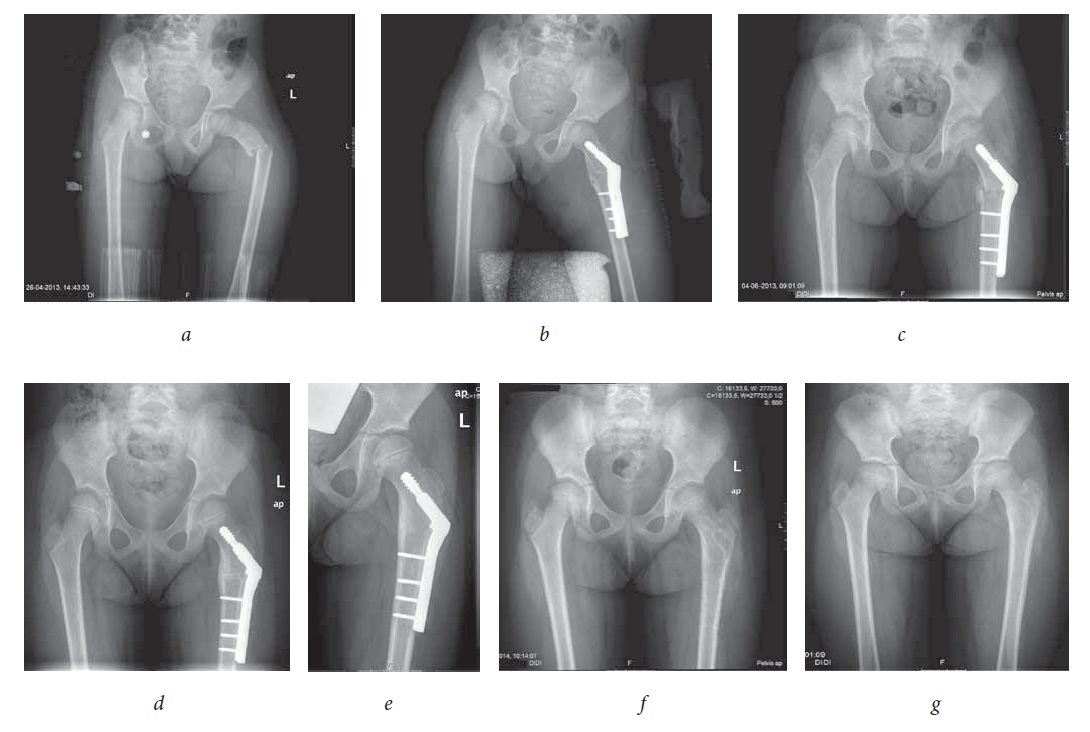

Admission radiographs showed a left proximal femur fracture and a left displaced proximal humeral fracture. The PHF was classified as a Delbet type 4 — extracapsular intertrochanteric fracture (Fig. 1, a).

Fig. 1. Delbet type IV extracapsular displaced intertrochanteric fracture. Radiograph: a — before operation; b — first day after operation; c — one month after operation; d — three months after operation; e — six months after operation; f — one month after the operation of removing the osteosynthesis material; g — fifteen months after the operation of removing the osteosynthesis material

She was put under cutaneous traction and analgesics.

On 2013/04/30 was submitted to open reduction and internal fixation with a pediatric sliding hip screw (SHS). The tip of the SHS did not invaded the physis, being positioned distally to it (Fig. 1, b).

The postoperative period was uneventful. She began the rehabilitation program with increased and progressive weightbearing exercises, after a 4-week-period of non-weightbearing (Fig. 1, c).

The osteosynthesis plate was removed 10 months after surgery (Fig. 1, d, e).

26 Months after the first surgery, radiographs revealed complete bone remodeling and no limb length discrepancy (Fig. 1, f, g). The range of motion (ROM) is painless and full.